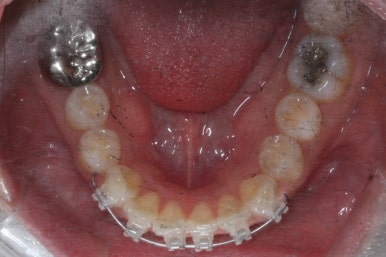

그리하여 부산앞니교정 키다리아저씨치과에서 장치를 재부착하고 일종의 재교정을 들어갔습니다.

유지장치를 하지 않은 상태였기 때문에 원래대로 앞니가 되돌아간 것을 볼 수 있습니다.

이번에는 약간 다른 양상으로 조절을 하기 위해서 MTA 장치 말고 일반 브라켓을 붙이기로 하였습니다.

이번에 사용한 장치는 클리피씨라고 하는 세라믹 자가결찰 장치였습니다.